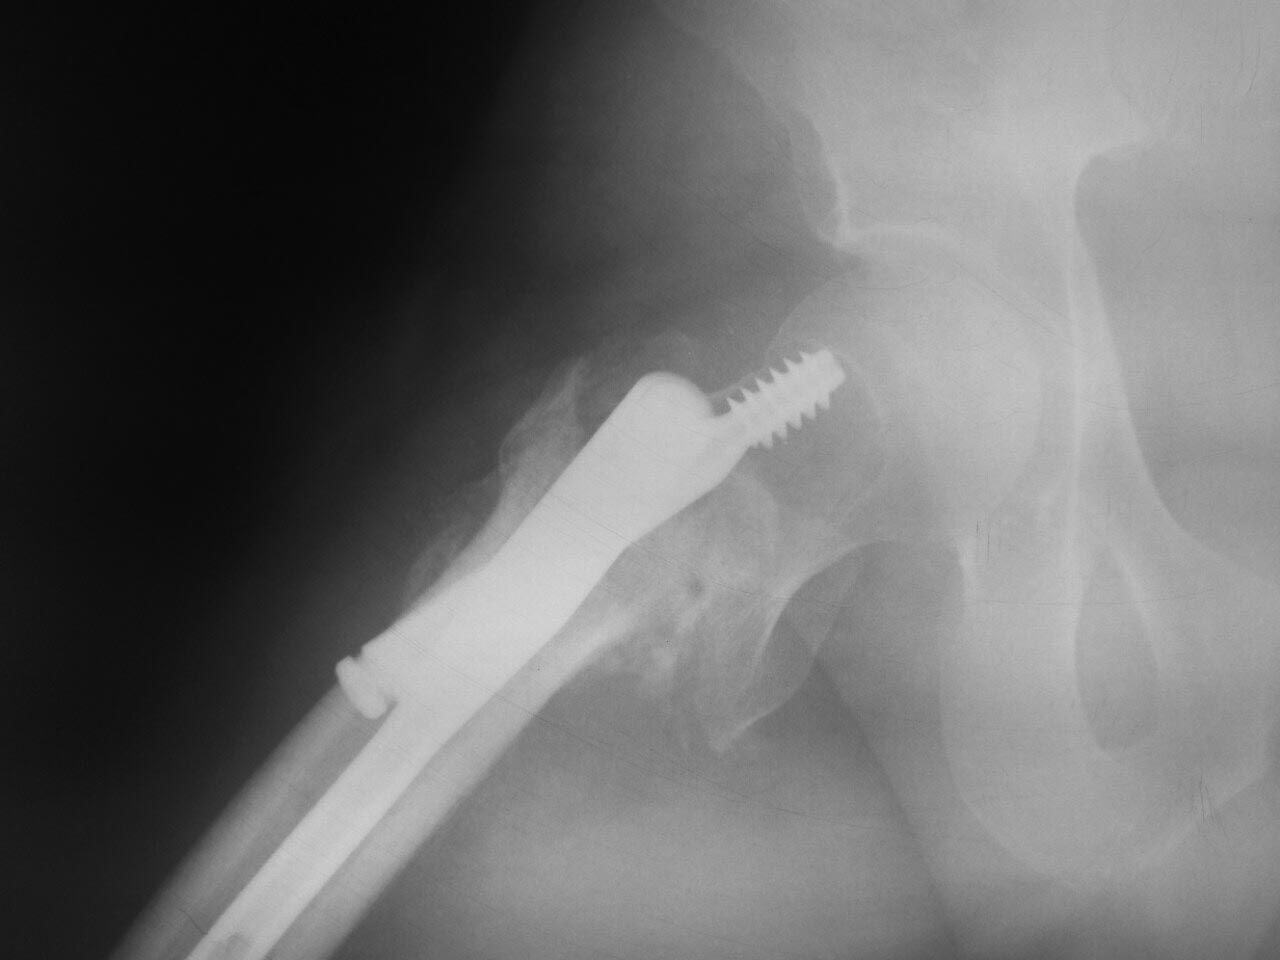

[Ortho] Выполнен остеосинтез Gamma3 1,5 мес назад

Аксиал